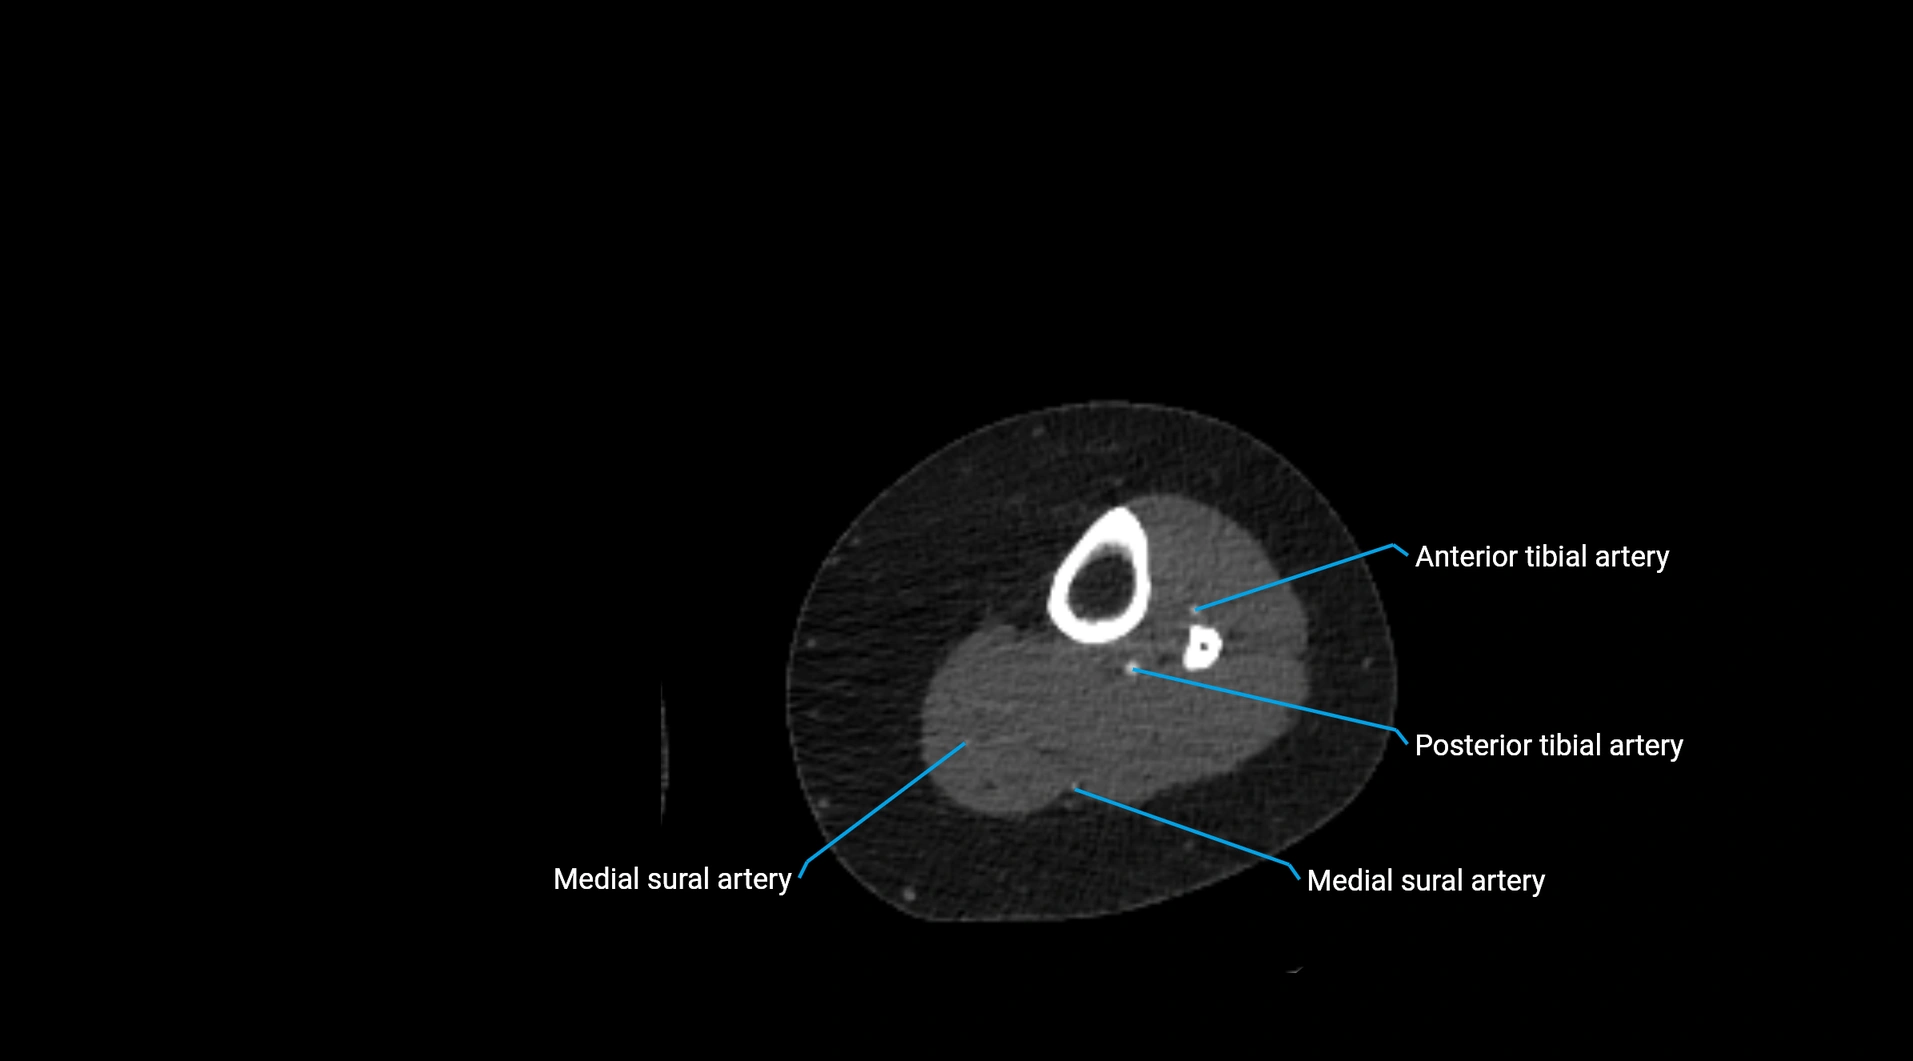

Contrast-enhanced CT (CTA):

• Gold standard for abdominal aortic imaging

• Provides excellent detail of lumen, wall, aneurysm, thrombus, and branch vessels

• Multiplanar and 3D reconstructions help in aneurysm measurement, stent graft planning, and dissection evaluation

• Detects acute rupture, traumatic injury, or occlusion with high sensitivity